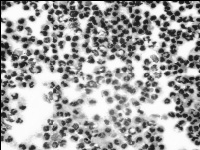

Как видно из диаграммы 1, на 4-ые сутки в экссудате из ран имеется повышение количества полиморфноядерных нейтрофилов и их дегенеративных форм, тогда как количество лимфоцитов снижается незначительно. На фотографиях цитограмм 2-го и 4-го дня отчетливо видна указанная динамика клеточных изменений (рис.1,2).

рис.1. Контрольная группа, 2-ой день |